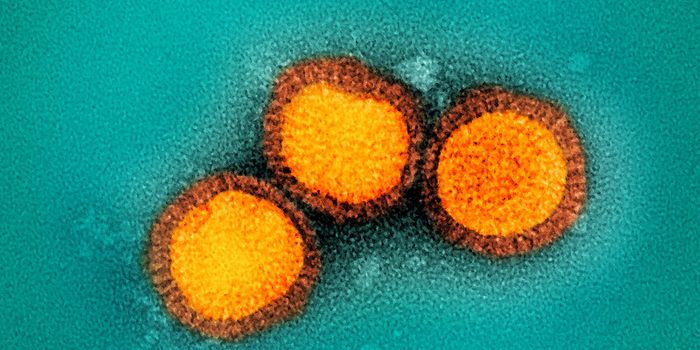

SEP 08, 2024MicrobiologySARS-CoV-2, the pandemic virus that causes COVID-19, has mutated endlessly since it burst on the scene in late 2019. An ...

AUG 27, 2024MicrobiologySince the start of the COVID-19 pandemic, the virus that causes the illness - SARS-CoV-2 - has had a practically infinit ...